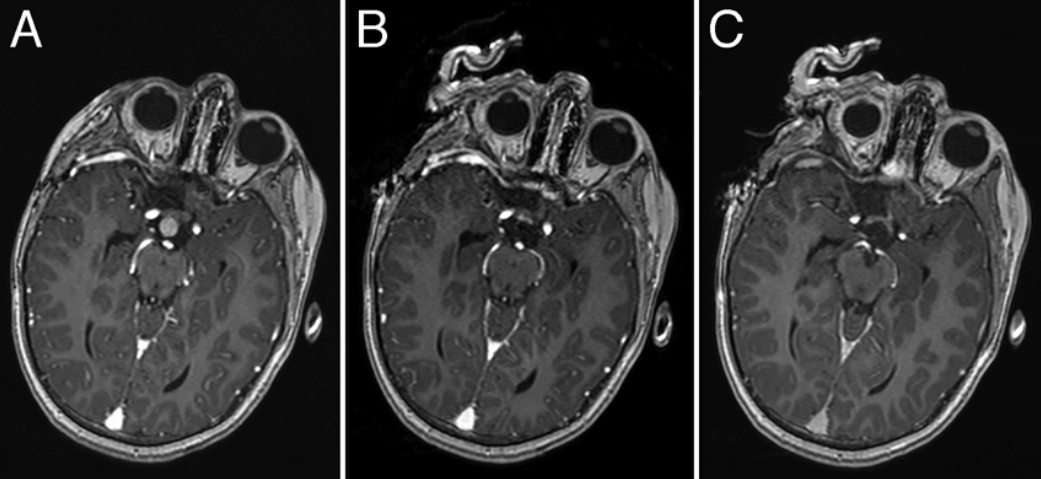

The use of high-field intraoperative MRI has been largely studied for the treatment of intracranial tumors in adult patients.In this study,the authors investigated the safety,advantages,and limitations of high-field iMRI for cranial neurosurgical procedures in pediatric patients,with particular attention to craniopharyngiomas and gliomas.METHODS The authors performed 82 surgical procedures in patients under 16 years of age(range 0.8-15 years)over an 8-year period using iMRI.The population was divided into 3 groups based on the condition treated:sellar region tumors(Group 1),gliomas(Group 2),and other pathological entities(Group 3).The patients'pre-and postoperative neurological status,the presence of residual tumor,the number of intraoperative scans,and complications were evaluated.RESULTS In Group 1,gross-total resection(GTR)was performed in 22(88%)of the procedures and subtotal resection(STR)in 3(12%).In Group 2,GTR,STR,and partial resection(PR)were performed,respectively,in 15(56%),7(26%),and 5(18%)of the procedures.In Group 3,GTR was performed in 28(93%)and STR in 2(7%)of the procedures.In cases of craniopharyngioma(Group 1)and glioma(Group 2)in which a complete removal was planned,iMRI allowed localization of residual lesions and attainment of the surgical goal through further resection,respectively,in 18%and 27%of the procedures.Moreover,in gliomas the resection could be extended from partial to subtotal in 50%of the cases.In 17%of the patients in Group 3,iMRI enabled the identification and further removal of tumor remnants.There was no intra-or postoperative complication related to the use of iMRI despite special technical difficulties in smaller children.In this study,the use of iMRI in children proved to be safe.It was most effective in increasing the extent of tumor resection,especially in patients with low-grade gliomas and craniopharyngiomas.The most prominent disadvantage of high-field iMRI was the limitation with respect to operative positioning due to the configuration of the surgical table.

结果:1组22例(88%)行全切除术,3例(12%)行次全切除术。2组分别有15例(56%)、7例(26%)和5例(18%)行GTR、STR和部分切除(PR)。3组28例(93%)行GTR,2例(7%)行STR。对于计划完全切除的颅咽管瘤(1组)和胶质瘤(2组),在18%和27%的手术中,iMRI允许定位残余病灶并通过进一步切除达到手术目的。此外,在胶质瘤中,50%的病例可以从部分切除扩大到次全切除。在3组中,17%的患者能够识别并进一步清除肿瘤残余物。